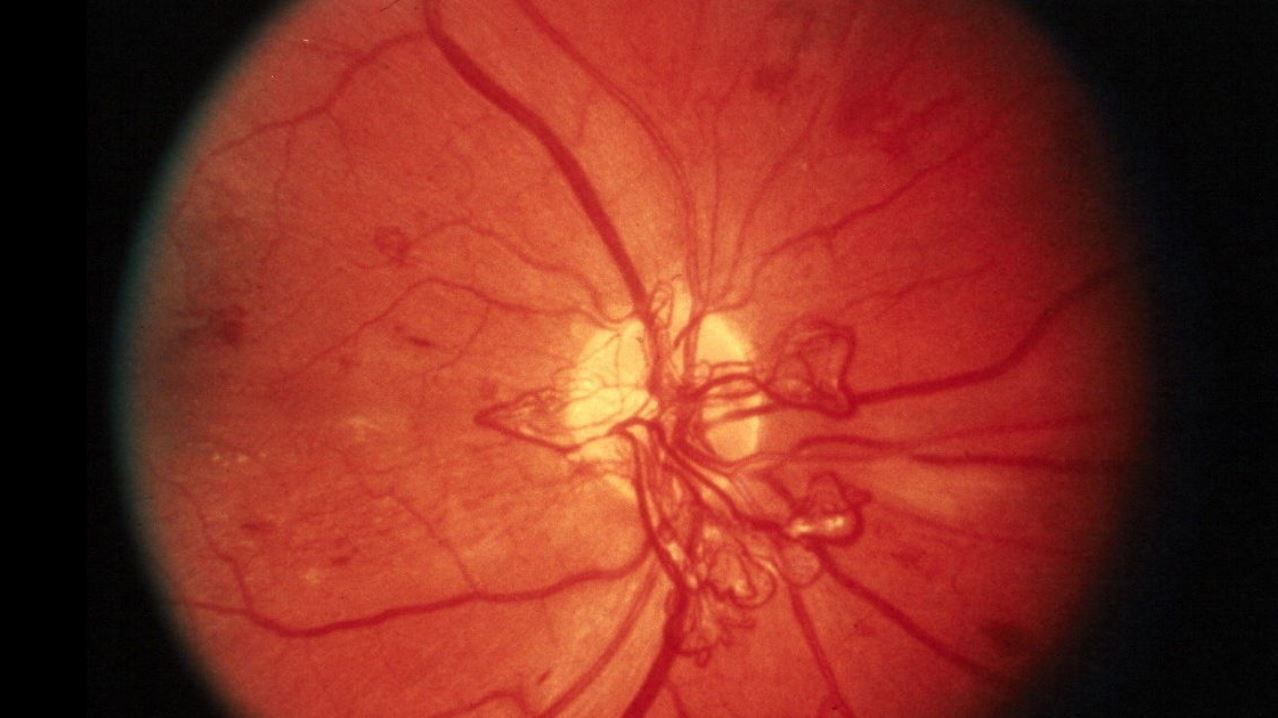

В настоящее время наиболее точными клиническими методами диагностики диабетической ретинопатии являются флуоресцентная ангиография и оптическая когерентная томография. Альтернативным и более дешевым методом является анализ изображений сетчатки глаза, который может быть сделан с помощью относительно недорогостоящего оборудования, называемого фундус-камерами, но этот процесс ручной, трудоемкий и менее надежный. Для автоматизации анализа изображений глазного дна группа исследователей из Мельбурнского королевского технологического университета разработала алгоритм обработки изображений на базе технологий искусственного интеллекта и глубокого обучения, который может автоматически определять один из ключевых признаков заболевания - наличие жидкости из поврежденных кровеносных сосудов или экссудата на сетчатке глаза - с точностью до 98%.